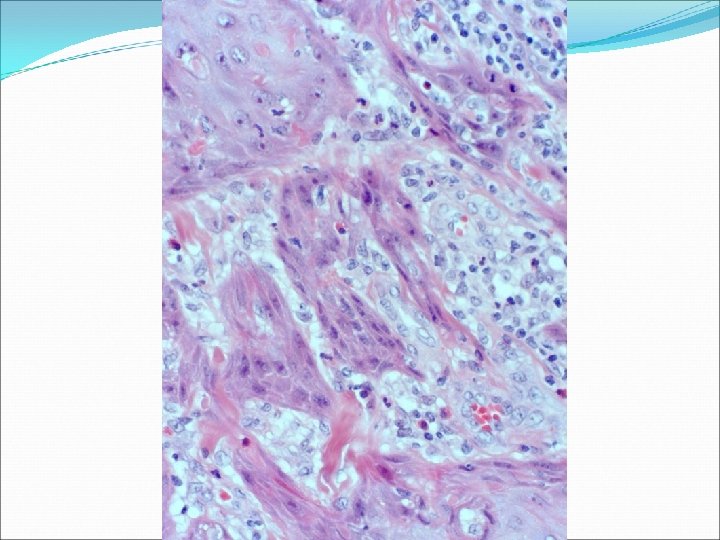

�Case number: 192 �Female aged 64 years. �Ultra sound 'vascular lump'. �Specimen: Lesion right

�Case number: 192 �Female aged 64 years. �Ultra sound 'vascular lump'. �Specimen: Lesion right neck. Excision �Macro: Skin ellipse 35 x 26 mm with raised smooth lesion 25 x 18 x 10 mm.

� Most popular diagnosis � Granular cell tumour